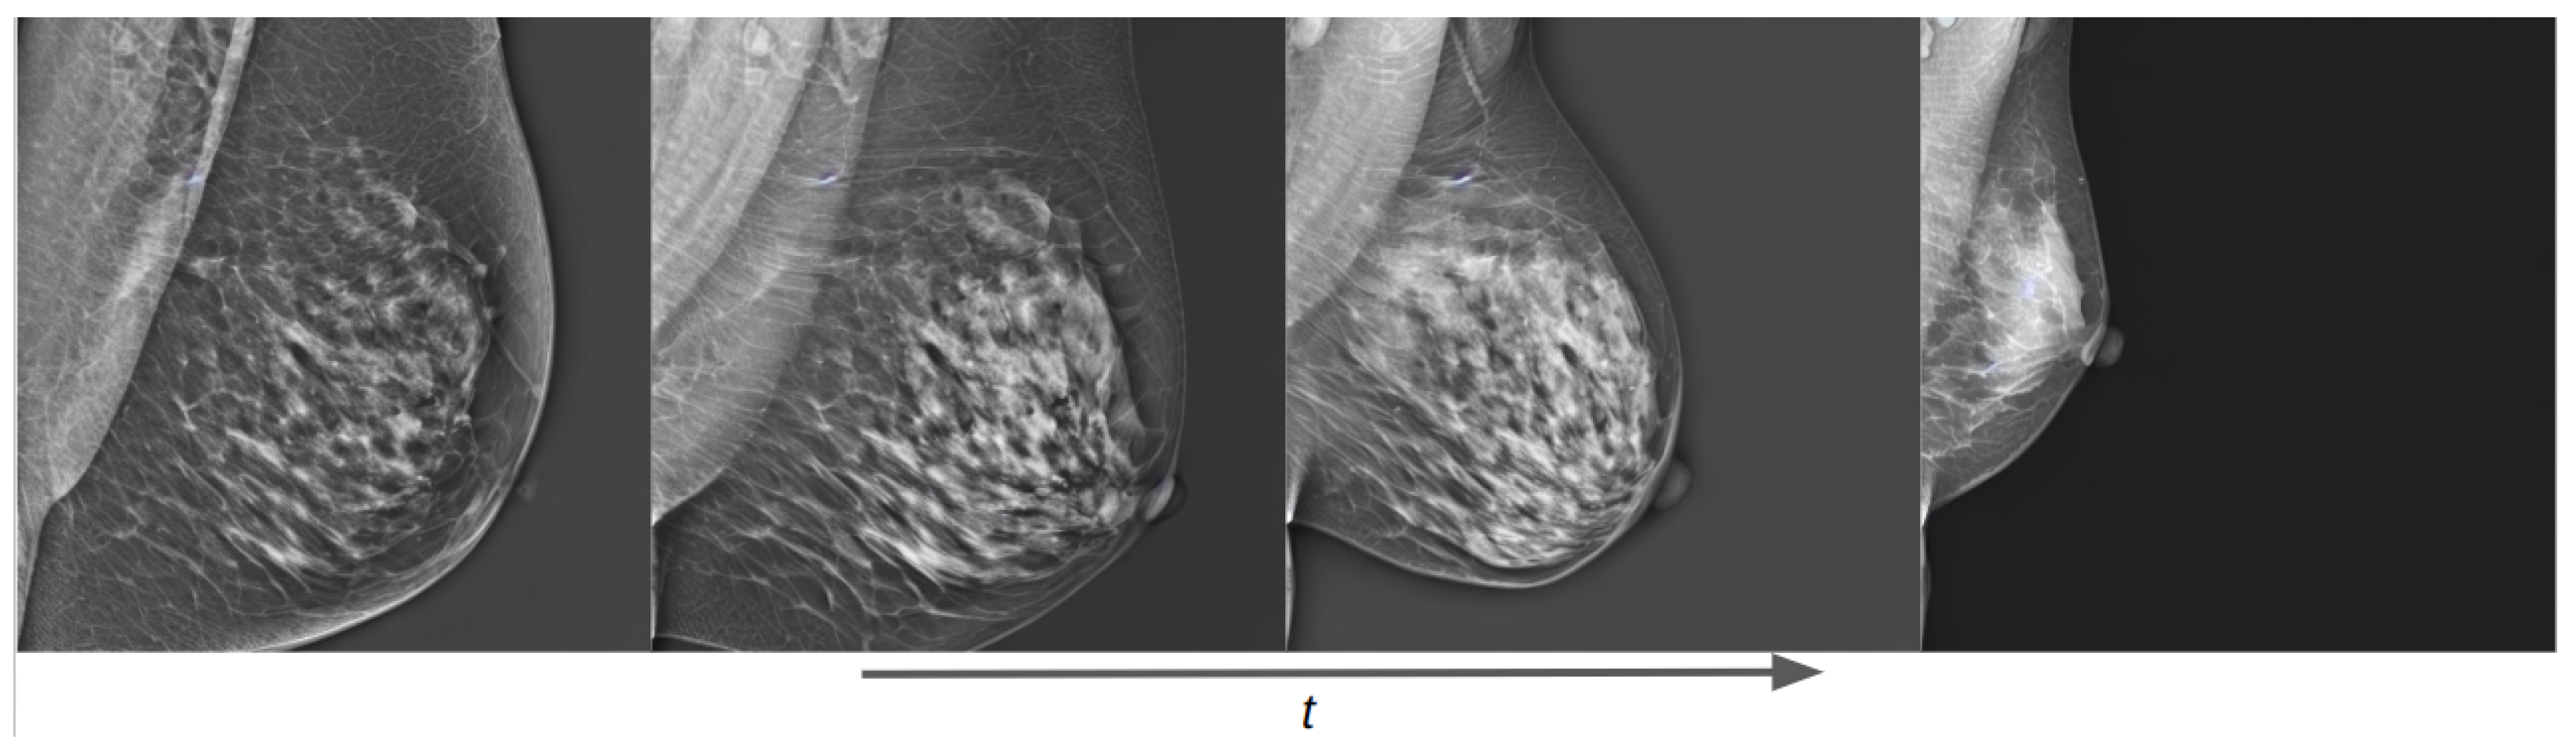

As an initial experiment, we trained an unconditional diffusion model with the Hologic dataset using the same text prompt for all images: “a mammogram”. The evolution of the diffusion process as the training steps progress is shown in Figure 12. It can be seen that from the first epoch the generated image has essentially no signs of residual Gaussian noise, although the synthetic image does not resemble a mammogram. This implies that diffusion models pretrained on natural images have learned to denoise images and that the new task is to learn a new concept by finding its representation in the data distribution of the model. We can also notice that in three epochs the model has learned the significant characteristics of a mammogram and can generate realistic images. In the following epochs, the model focuses on improving smaller details on the image, such as the edges of the breast and the details of the breast parenchyma.

Figure 12.

Training evolution of the diffusion process on an unconditional pretrained model at epochs 1, 3, 6, and 10.